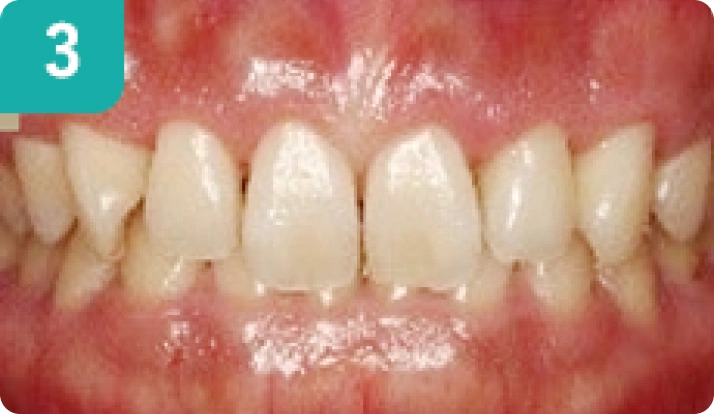

上前歯が小さいのとガミースマイルを歯肉整形にて改善しました。上前歯の縦長さが短めで歯が小さく見えて歯肉ラインが不揃いでした。歯肉整形をすることで、口元からの歯の見え方が整ってスマイル時の印象が良くなりました。

【治療期間】2週間 【費用】80,000円(税別) 【リスク・副作用】術後2~5日程は傷口に赤みが見えたり、痛みが生じる場合があります。当院で行う歯肉整形は歯と歯肉、歯槽骨に対して行う処置であり、入院が必要な骨切り手術(Le Fort手術)などは対応していません。